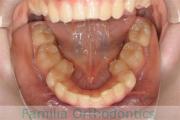

No.22V-562

- 叢生

- 28歳

- 女性

- 上:

- 448

- 下:

- 44

- FEA 022

- 88万円

前歯のでこぼこを治したいということで来院されました。非常に強い叢生(でこぼこ、凹凸、ガタガタ)でしたので、上下左右から小臼歯を抜歯して、マルチブラケット法にて治療を行いました。2年強、25回程度の通院をしていただきました。

上下とも叢生(でこぼこ、凹凸、ガタガタ)が強いため、後戻りのリスクが高くなると考えられます。